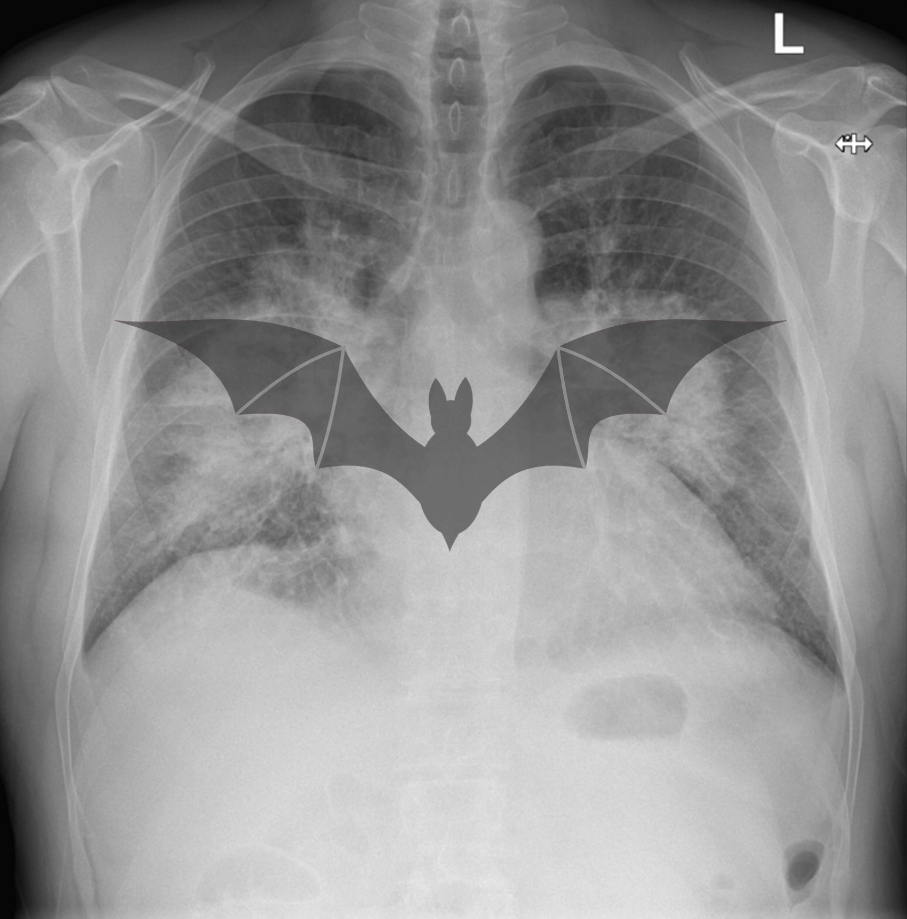

• When fluid accumulation is rapid you may get the classic ‘bat wing’ appearance like the X-Ray below.

In this separate case there is rapid fluid accumulation leading to a classic bat wing appearance of pulmonary oedema.